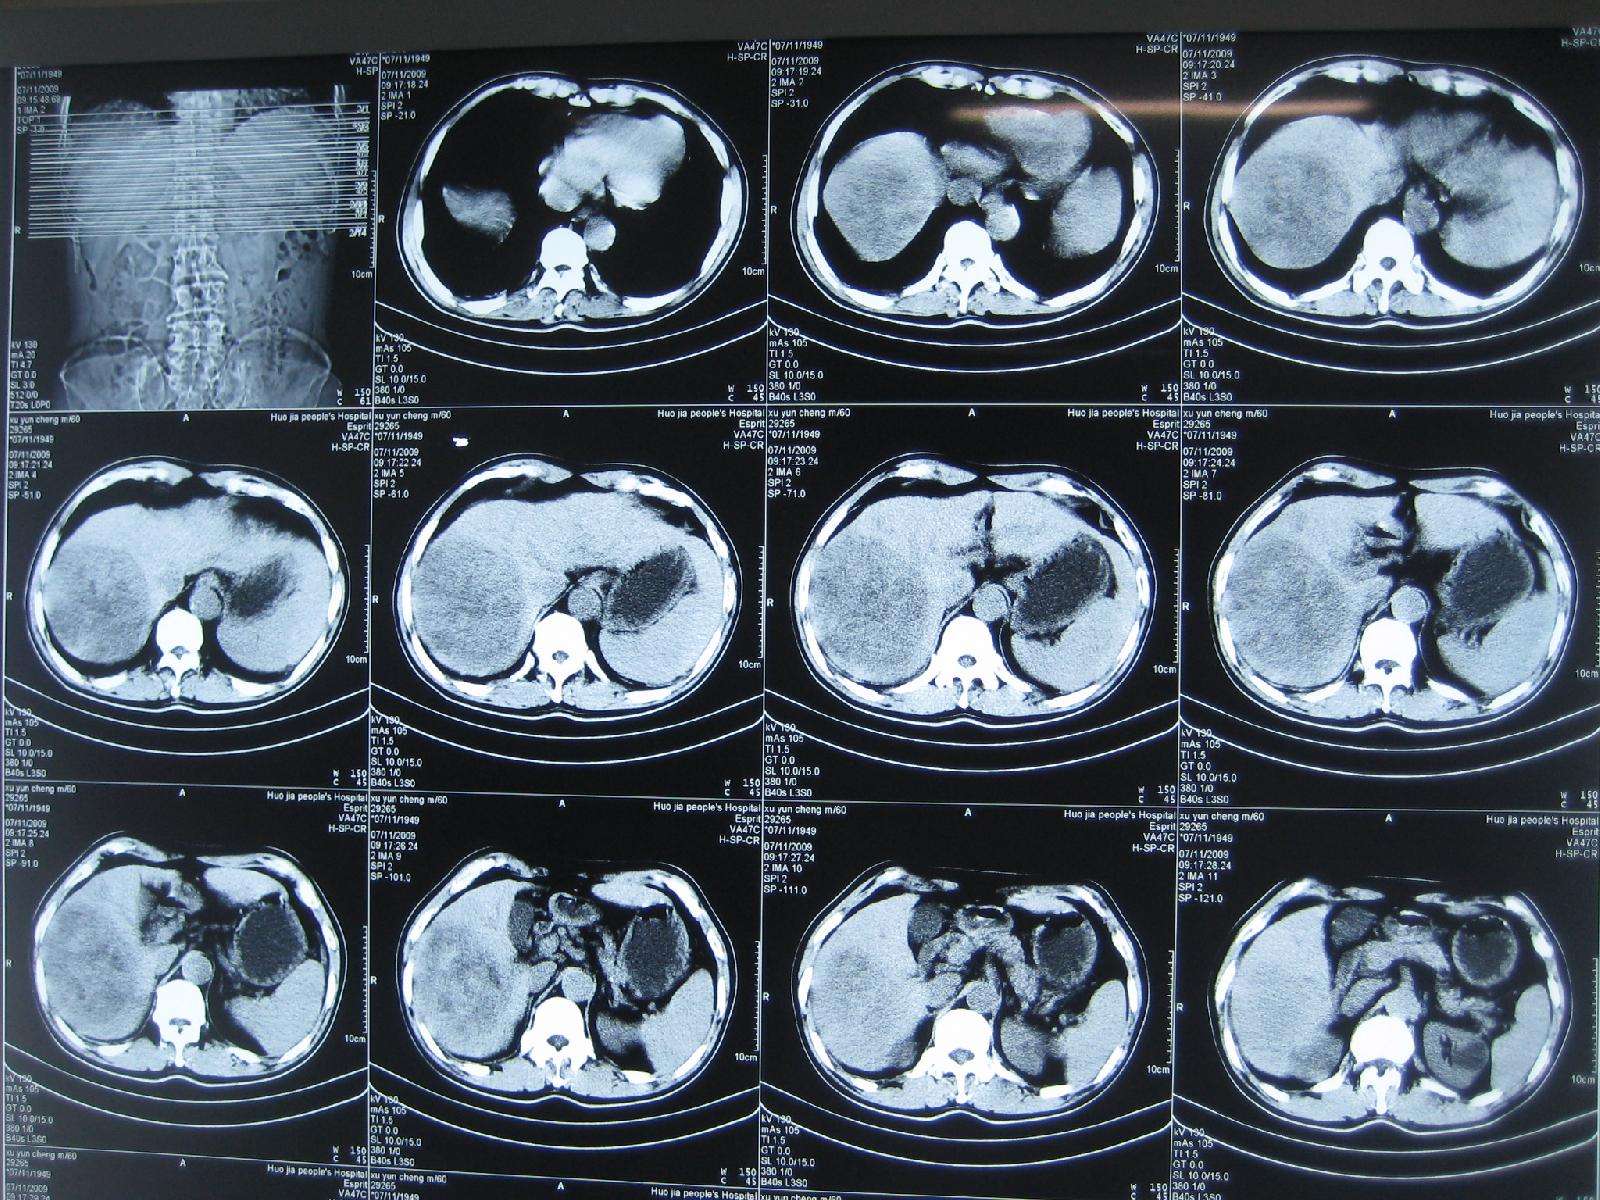

【喜讯】楚雄州人民医院首例完成经介入治疗为中晚期巨块型肝癌患者

图片尺寸2667x2000